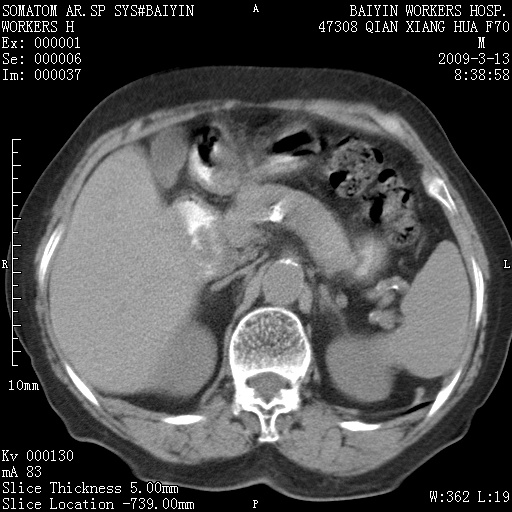

标题: CT18651:左肾上腺占位,请会诊!

女,70岁,体检发现。

左肾上腺腺瘤

左侧肾上腺结节状软组织密度影;考虑肿瘤(肾上腺腺瘤?转移瘤?)。

左侧肾上腺占位,腺瘤?不除外转移。

左侧肾上腺占位,腺瘤可能。

左侧肾上腺占位,考虑腺瘤可能。